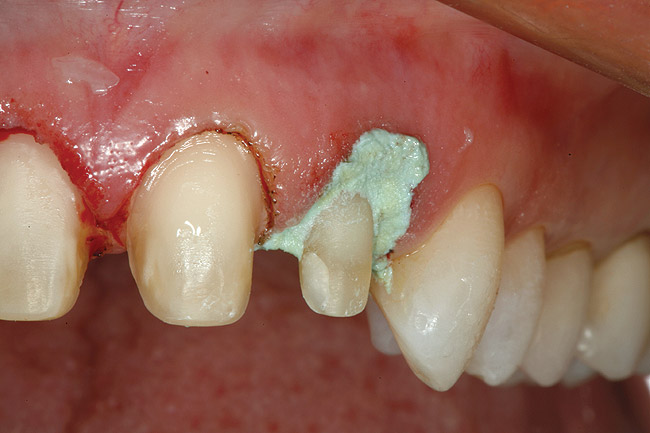

Figure 16  After initial positioning of the bone, keeping the tip of the laser in intimate contact with the root surface, a slight troughing of the bone was seen on radiographic examination.

Figure 16